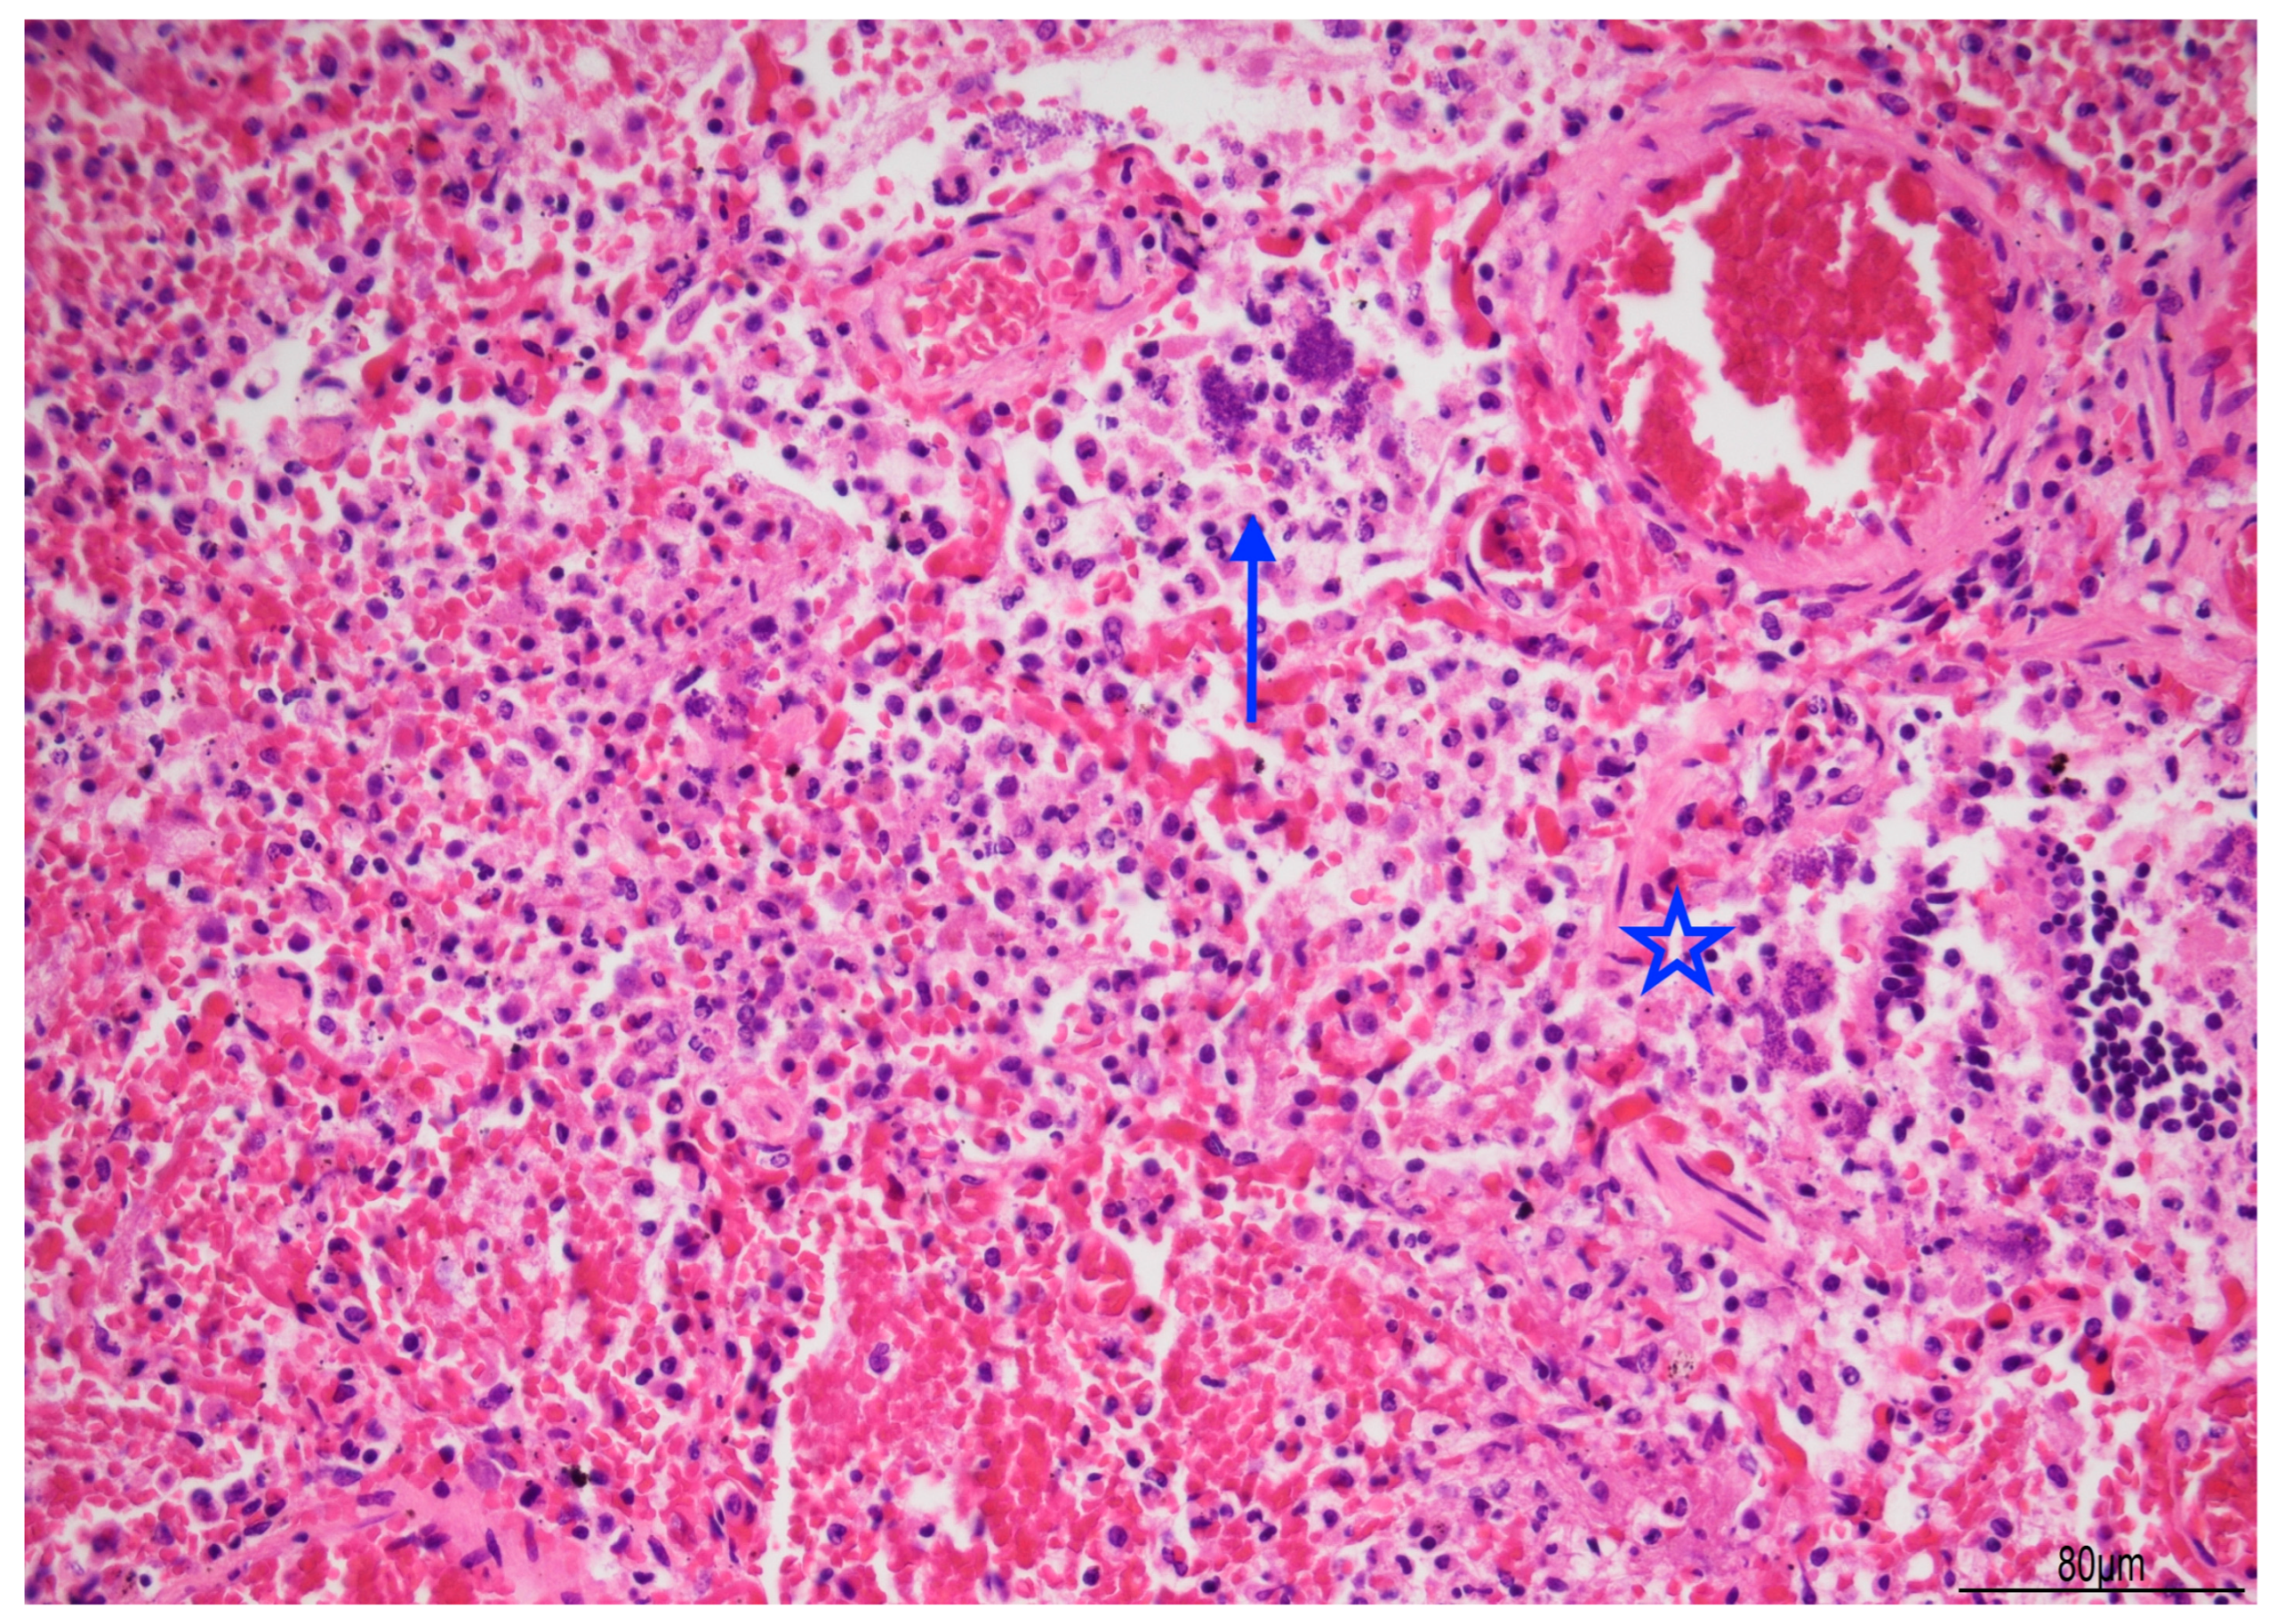

Lung histology revealed acute exudative pneumonia with abundant neutrophils, fibrin deposition, intra-alveolar hemorrhage, bacterial colonies (cocci), abundant lipid-laden macrophages (compatible with early lipoid pneumonia), and focal foreign-body giant cell reaction to aspirated material (Figure 7, Figure 8 and Figure 9). Histochemistry for PAS, PAS-D, and Grocott were performed to rule out fungal colonization and resulted negative.

Figure 7. Acute pneumonia: alveoli were filled with neutrophils and bacteria (blue arrow). Bacteria were also found in bronchioles (star). Abundant erythrocytes within the alveoli were also present (Hematoxylin and Eosin, 20 HPF).